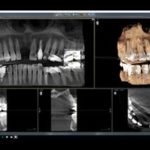

次に、立体的なレントゲン写真(CT)撮影と歯型を取らせていただき、実際に歯を作る位置を決めます。